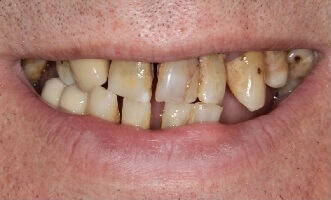

Проблема. Множественные кариозные поражения зубов, высокая степень подвижности зубов

Решение. Из-за плохого стоматологического прогноза оставшиеся зубы были удалены, а в верхнюю и нижнюю челюсти были установлены четыре зубных имплантата. На имплантаты установлены металлокерамические коронки.